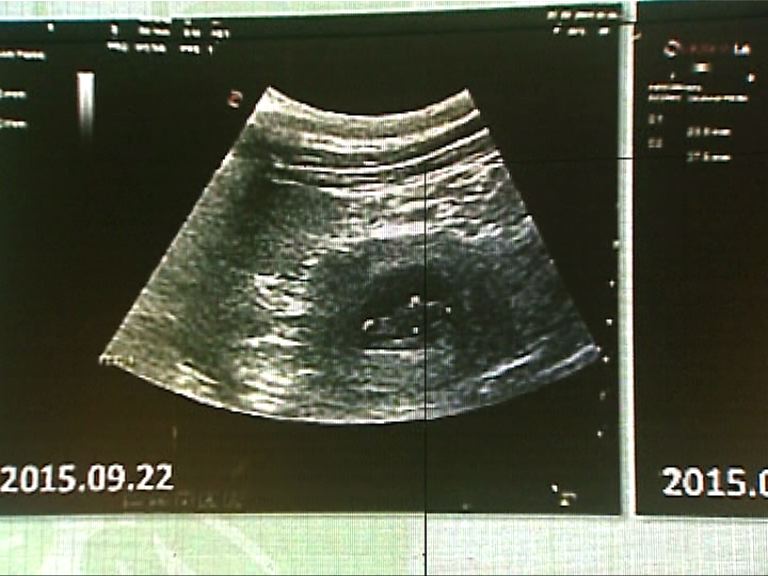

海洋公園大熊貓護理團隊在7月下旬,首先發現盈盈的荷爾蒙水平有變及食量下降等懷孕迹象,直至上月22日以超聲波掃瞄時發現有胎兒。目前熊貓胎兒體長約3.5厘米,預計一星期內分娩,但專家表示胎兒仍有風險。